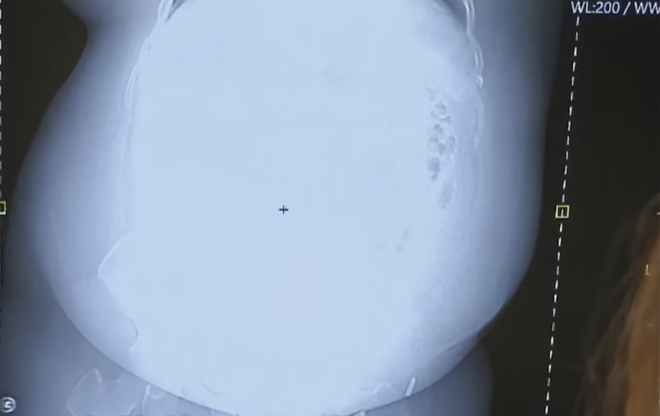

良子的X光片也极具艺术性。

放射线在大胃袋面前也略显乏力,无法穿透脂肪下面的内脏,X光片显示的结果是一团白雾,再资深的医生看了良子的X光片都要冒几滴冷汗,网友建议“不如直接换成伽马射线吧”。